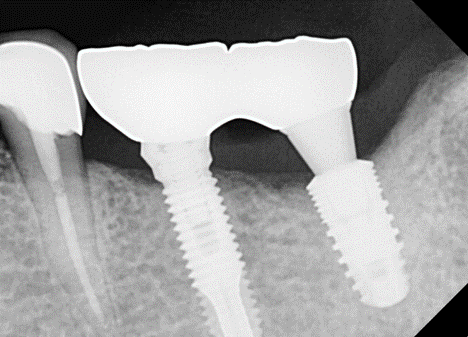

ÀÌ ÀÓ»ó ÄÉÀ̽º´Â ºê¸´Áö ŸÀÔÀ»

½Ì±Û ŸÀÔÀ¸·Î ¹Ù²ãÁÖ±â À§ÇÑ ÀÛ¾÷ Áß ÀÏ¾î³ ÀÛÀº ¼Òµ¿À» ±â·ÏÇß´Ù.

¾î¹þÀ» Ç®´Ù°¡ Ç÷¿Æû¿¡ ÀÖ´Â

Çí»ç°¡ ¸Á°¡Á³´Ù. Ç® ¼ö°¡ ¾ø¾ú´Ù. 4.4 mm ³»°æÀ» °¡Áø solid ab ü°á µå¶óÀ̺긦 ÀÌ¿ëÇϱâ·Î Çß´Ù.

¸ÕÀú Ezc ¾î¹þÀÇ Á÷°æÀ» ´ÙÀ̾Ƹóµå ¹ö·Î »ì¦ ´ÙµëÀº ´ÙÀ½, ½½·ÔÀ» ¸¸µé°í, À̰÷¿¡ solid ab µå¶óÀ̹ö°¡ »ðÀԵǵµ·Ï ÇÑ´Ù. µ¹¸®¸é ½±°Ô Á¦°ÅµÈ´Ù.